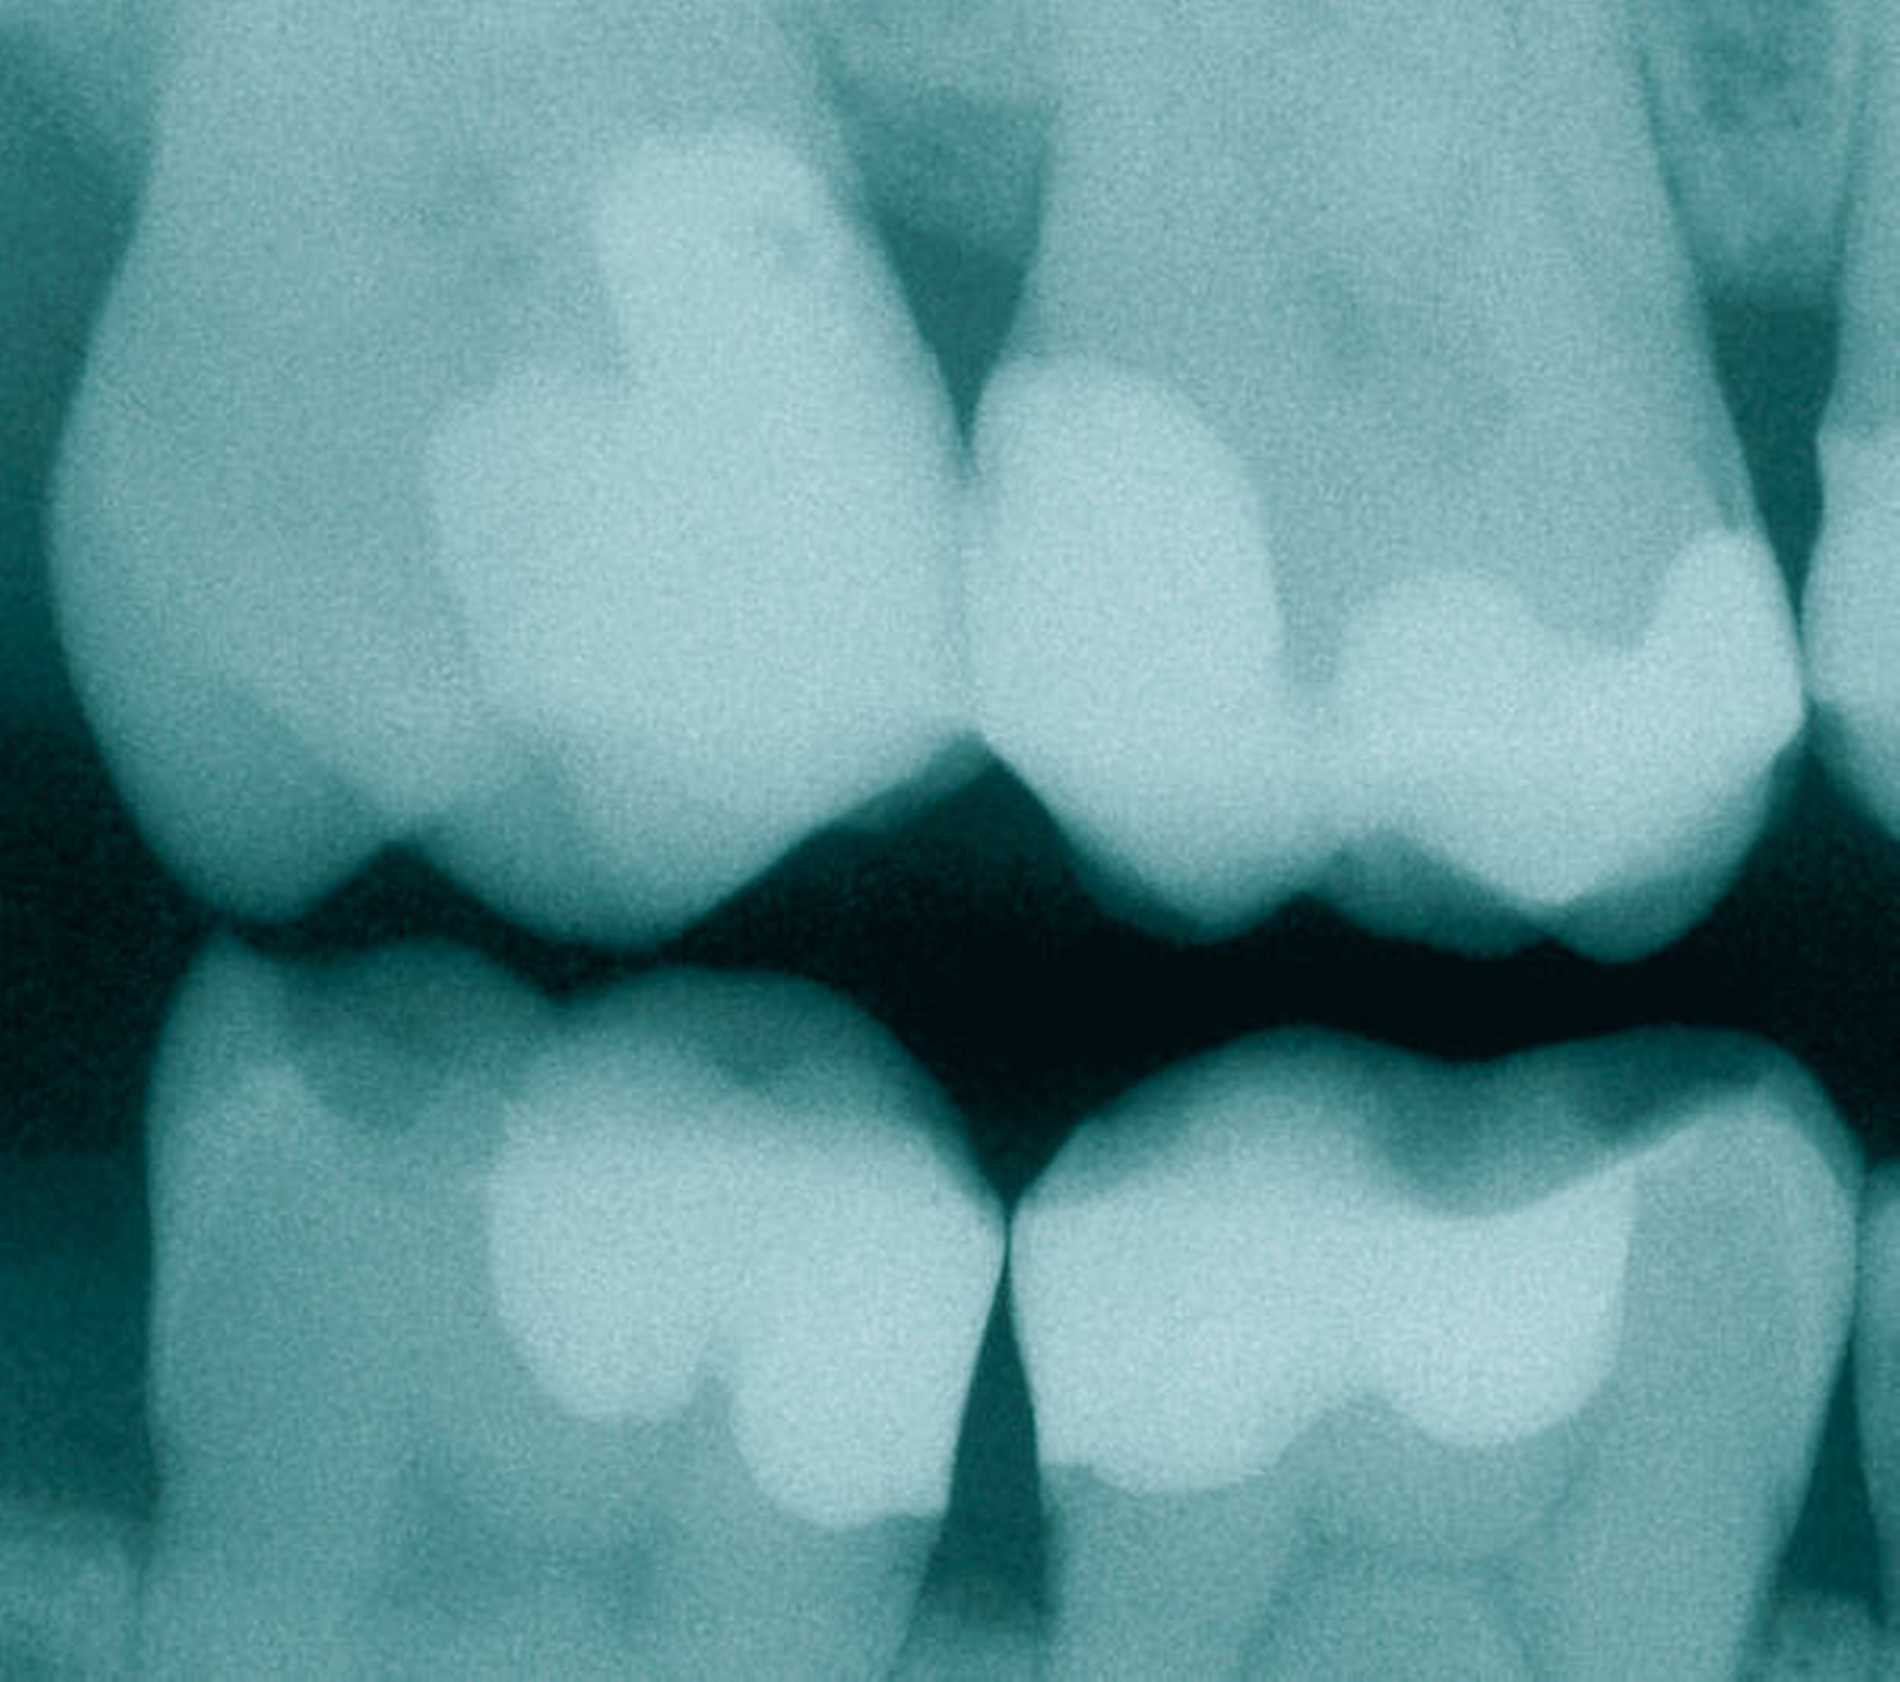

- Minimalinvasivität: Der bedingungslose Respekt vor gesunder Zahnhartsubstanz ist durch Schmelz- und Dentinbonding erst klinisch umsetzbar geworden [van Meerbeek et al., 2003]. Obwohl Minimalinvasivität weit mehr bedeutet als „kleine Löcher zu bohren“ – Exkavation, Nachhaltigkeit und Reparabilität sind ebenso wichtig –, ist sie in der Majorität der Fälle dem obsoleten „Extension for Prevention“ überlegen [Frankenberger et al., 2014] (Abbildung 1).

Jeder Zahnarzt hat ein spezielles Verhältnis zu seinem verwendeten Adhäsivsystem, da es täglich zum Einsatz kommt und Misserfolge schmerzlich sind. Bei der Auswahl des individuellen Bondings sind verschiedene Mechanismen zu beobachten, so dass beispielsweise sehr oft dasjenige Adhäsivsystem verwendet wird, das im Studium an der Universität verwendet wurde – zumindest dann, wenn man damit gute Erfahrungen gemacht hat. Ein für sehr lange Zeit beobachtbarer Trend war der Hang zu vermeintlich schnelleren Adhäsiven aus einer Flasche. Heute weiß man mehr denn je, dass 60 Sekunden Adhäsivtechnik die Grundlage einer mehrjährigen Lebensdauer von gebondeten Restaurationen sind (Abbildung 2).

Regel Nr. 1 sollte daher sein, in diesen 60 Sekunden möglichst wenig falsch zu machen – Zeitsparen gehört hier nicht hin, denn gerade im Rahmen der adhäsiven Vorbehandlung wird ein wichtiges Fundament für jegliche Restauration geschaffen (Abbildung 3).